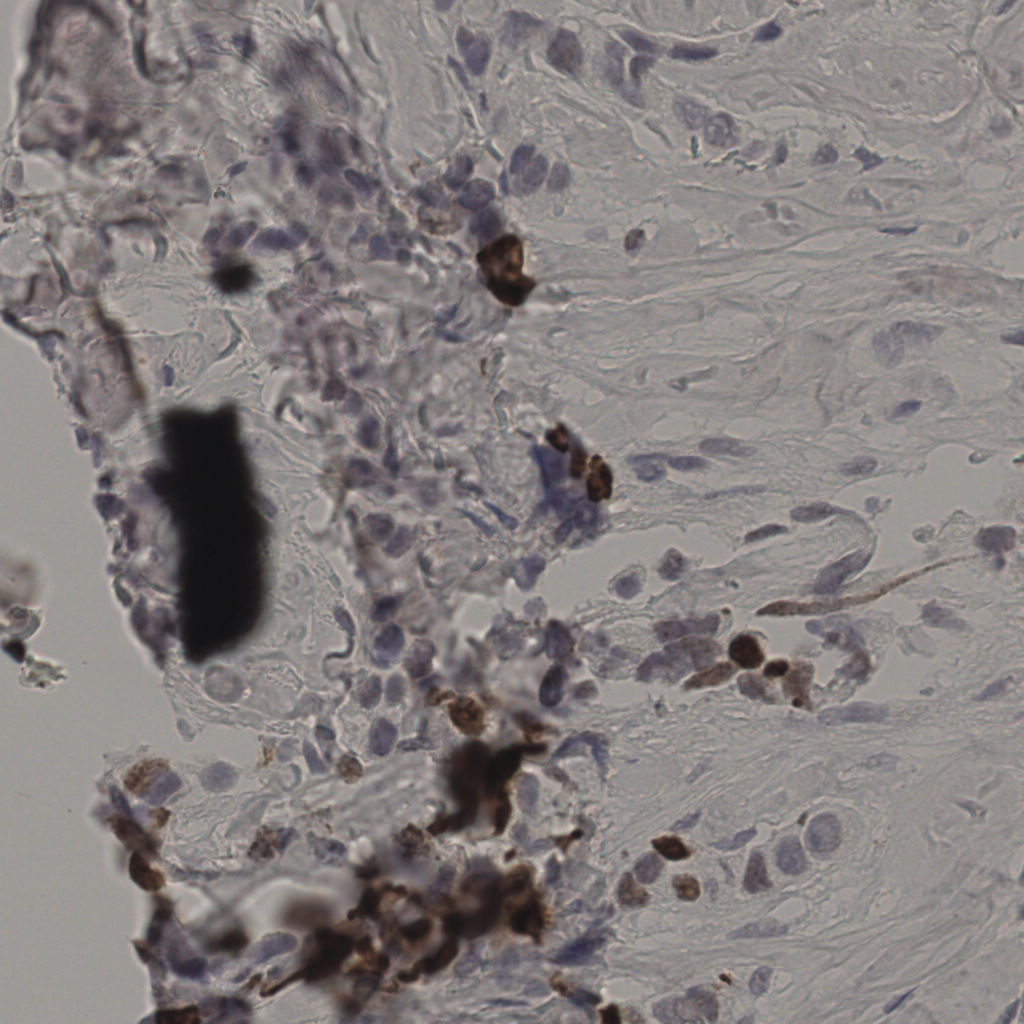

缩略图

标记后

标记前